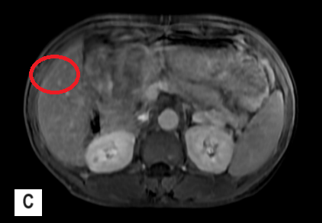

- Cộng hưởng từ gan mật có tiêm thuốc:

Hình ảnh nhu mô gan hạ phân thùy S5 có nốt đường kính 8,5mm tăng nhẹ tín hiệu trên T2W, hạn chế khuếch tán trên DWI, ngấm thuốc mạnh thì động mạnh, có phần thải thuốc thì tĩnh mạch và thì muộn. Tĩnh mạch cửa không giãn, không thấy huyết khối.

Hình 2: Hình ảnh MRI ổ bụng:  nốt hạ phân thùy S5 (vòng tròn màu đỏ) (A: thì động mạch, B: thì tĩnh mạch, C: thì muộn)